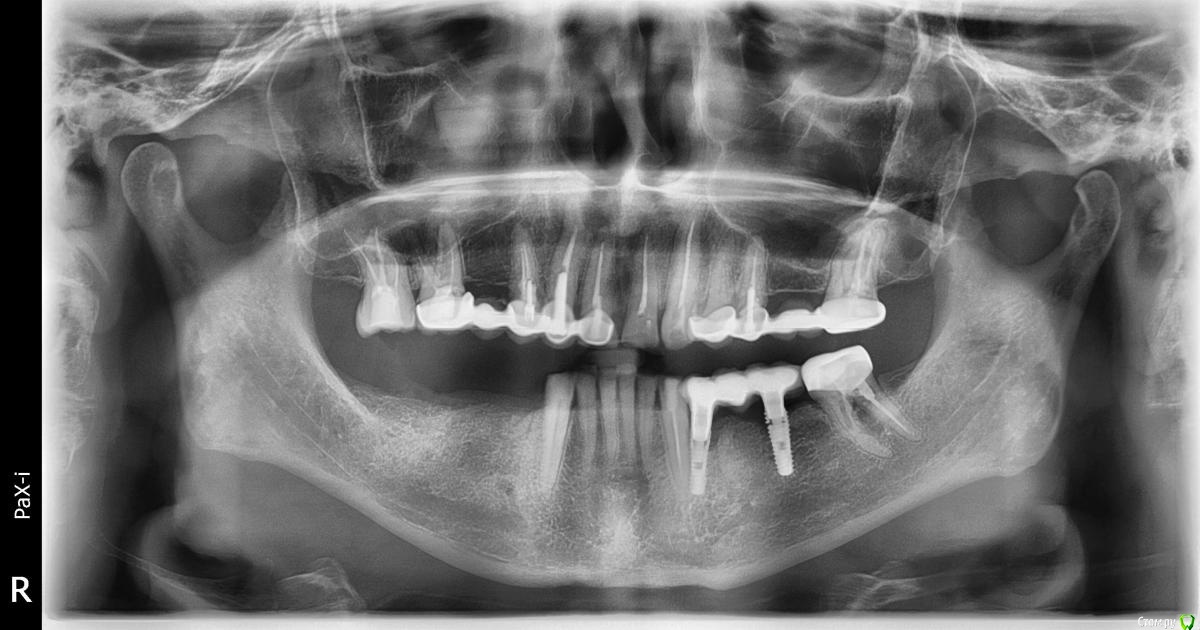

В апреле 2020 года была проведена имплантация на месте 34 и 36 зубов (корейская система INNO implant submerged 3.5x12, 4.0х12).

В июле 2020 года на импланты был установлен металлокерамический мост на приливаемых абатментах (винтовая фиксация). По состоянию на 20.11.2020 (4 месяца под нагрузкой) жалоб не было.

22.01.2020 ослабли винты на имплантах, был сделан новый снимок, где обнаружилось, что имплант на месте 36 сломался.

Снимки прилагаю.

post-62133-0-73471000-1611750751_thumb.jpg